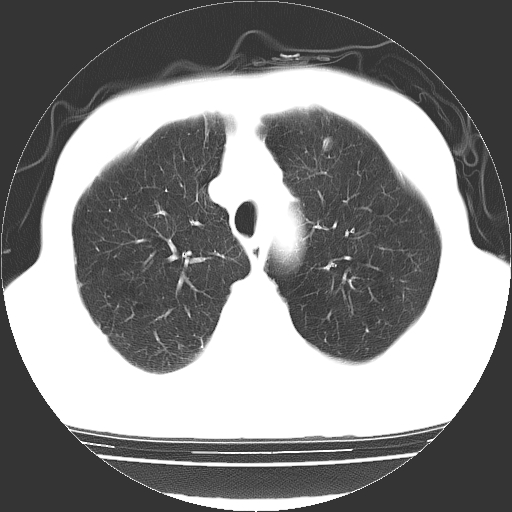

以下是引用hhcckk在2009-1-1 15:38:00的发言:[br]左下肺少许絮状模糊影--考虑感染[br]两肺散在小点状密度增高影--结合病史考虑矽肺?[br]气管壁钙化--可能由于老年退变性引起的